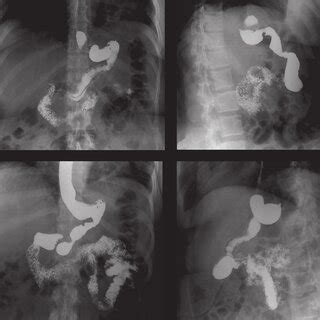

Estudio del Tubo Digestivo Alto Post-Bypass Gástrico (BPG)

En el caso de los pacientes operados de BPG, el estudio se enfoca en el reservorio gástrico y la anastomosis gastroenteral. Se evalúa el volumen del remanente gástrico, estimado en relación al cuerpo vertebral T12, y la presencia de filtraciones o dificultad al vaciamiento.

- Hallazgos radiológicos normales: La banda gástrica ajustable (si se utilizó) debe tener un ángulo phi entre 4-58º. El diámetro máximo de la cámara superior no debe superar los 3-4 cm (15-20 cc) y vaciarse entre 15-20 minutos. La nueva cámara gástrica debe ser del tamaño de un cuerpo vertebral.

- Complicaciones: Se vigila la presencia de filtración del medio de contraste a nivel de la anastomosis gastroenteral y la dificultad al vaciamiento del remanente gástrico, definida como retención del medio de contraste por más de un minuto.

- Hallazgos radiológicos normales: El estómago se observa tubular, largo y delgado, sin evidencia de fugas ni torsión. Se muestra adecuado vaciamiento gástrico y paso del contraste hacia el duodeno e intestino delgado.

- Complicaciones: La filtración del medio de contraste puede ocurrir a nivel de la línea de sutura en la curvatura mayor, siendo la porción cefálica de esta línea de sutura un sitio frecuente. Se evalúa la presencia de colecciones líquidas adyacentes a la línea de sutura.